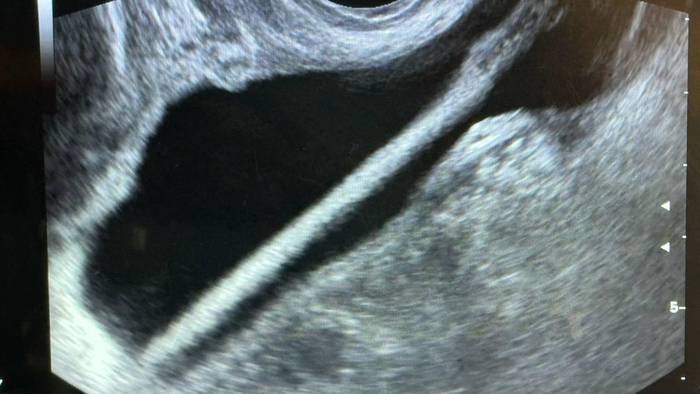

Фото: Министерство здравоохранения Московской области

Врачи Красногорской больницы спасли 46-летнюю пациентку, достав из ее мочевого пузыря косметический карандаш. Об этом в среду, 11 февраля, сообщила пресс-служба Министерства здравоохранения Московской области.

Как сообщил заведующий урологическим отделением Красногорской больницы Петр Сысоев, женщине сделали УЗИ, после этого провели операцию, в ходе которой удалили карандаш с помощью эндоскопа.